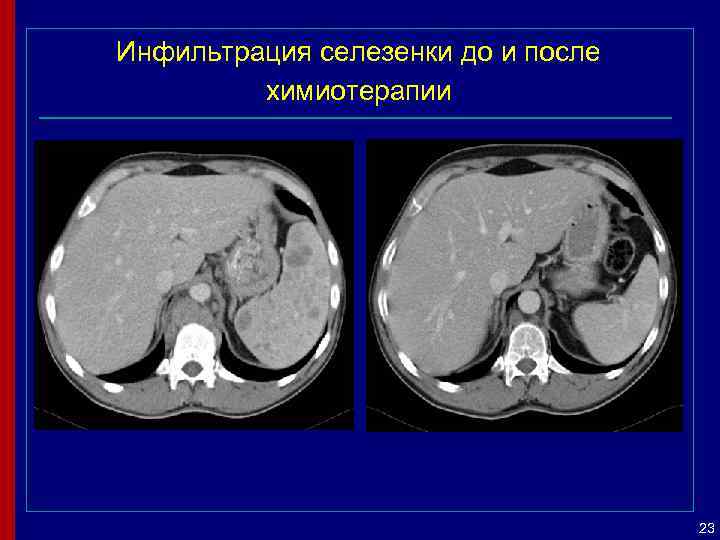

Инфильтрация селезенки до и после химиотерапии 23